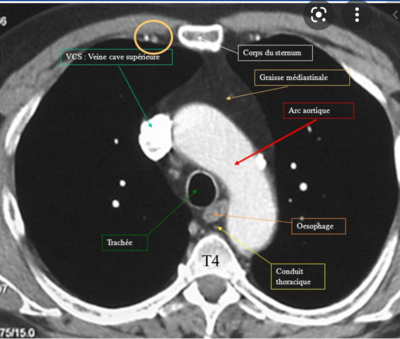

QCM 3 : À propos de la coupe en T4 on peut retrouver, indiquez la ou les bonne(s) réponse(s) :

ACD

Concernant la D, j'ai un doute. En T4, on est à la jonction manubrium/corps, donc on compte juste :